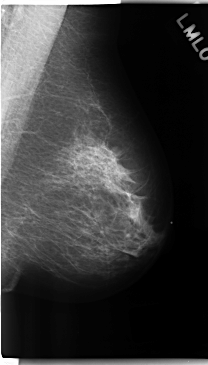

C_0225_1.LEFT_MLO

LEFT_MLO LINES 4744 PIXELS_PER_LINE 2696 BITS_PER_PIXEL 12 RESOLUTION 50 NON_OVERLAY